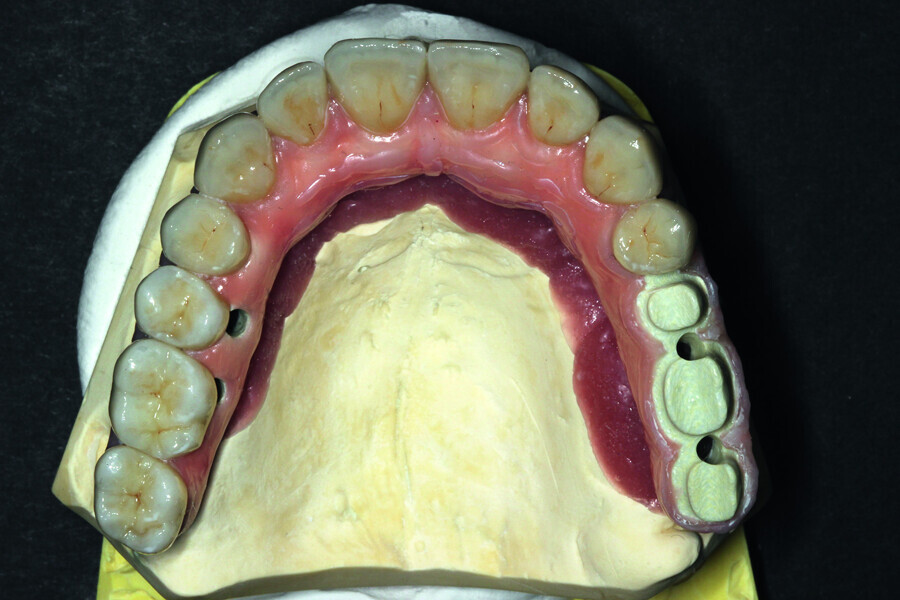

Fig. 20: Prosthetic work based on a model where veneering of the gum was started and with crowns.